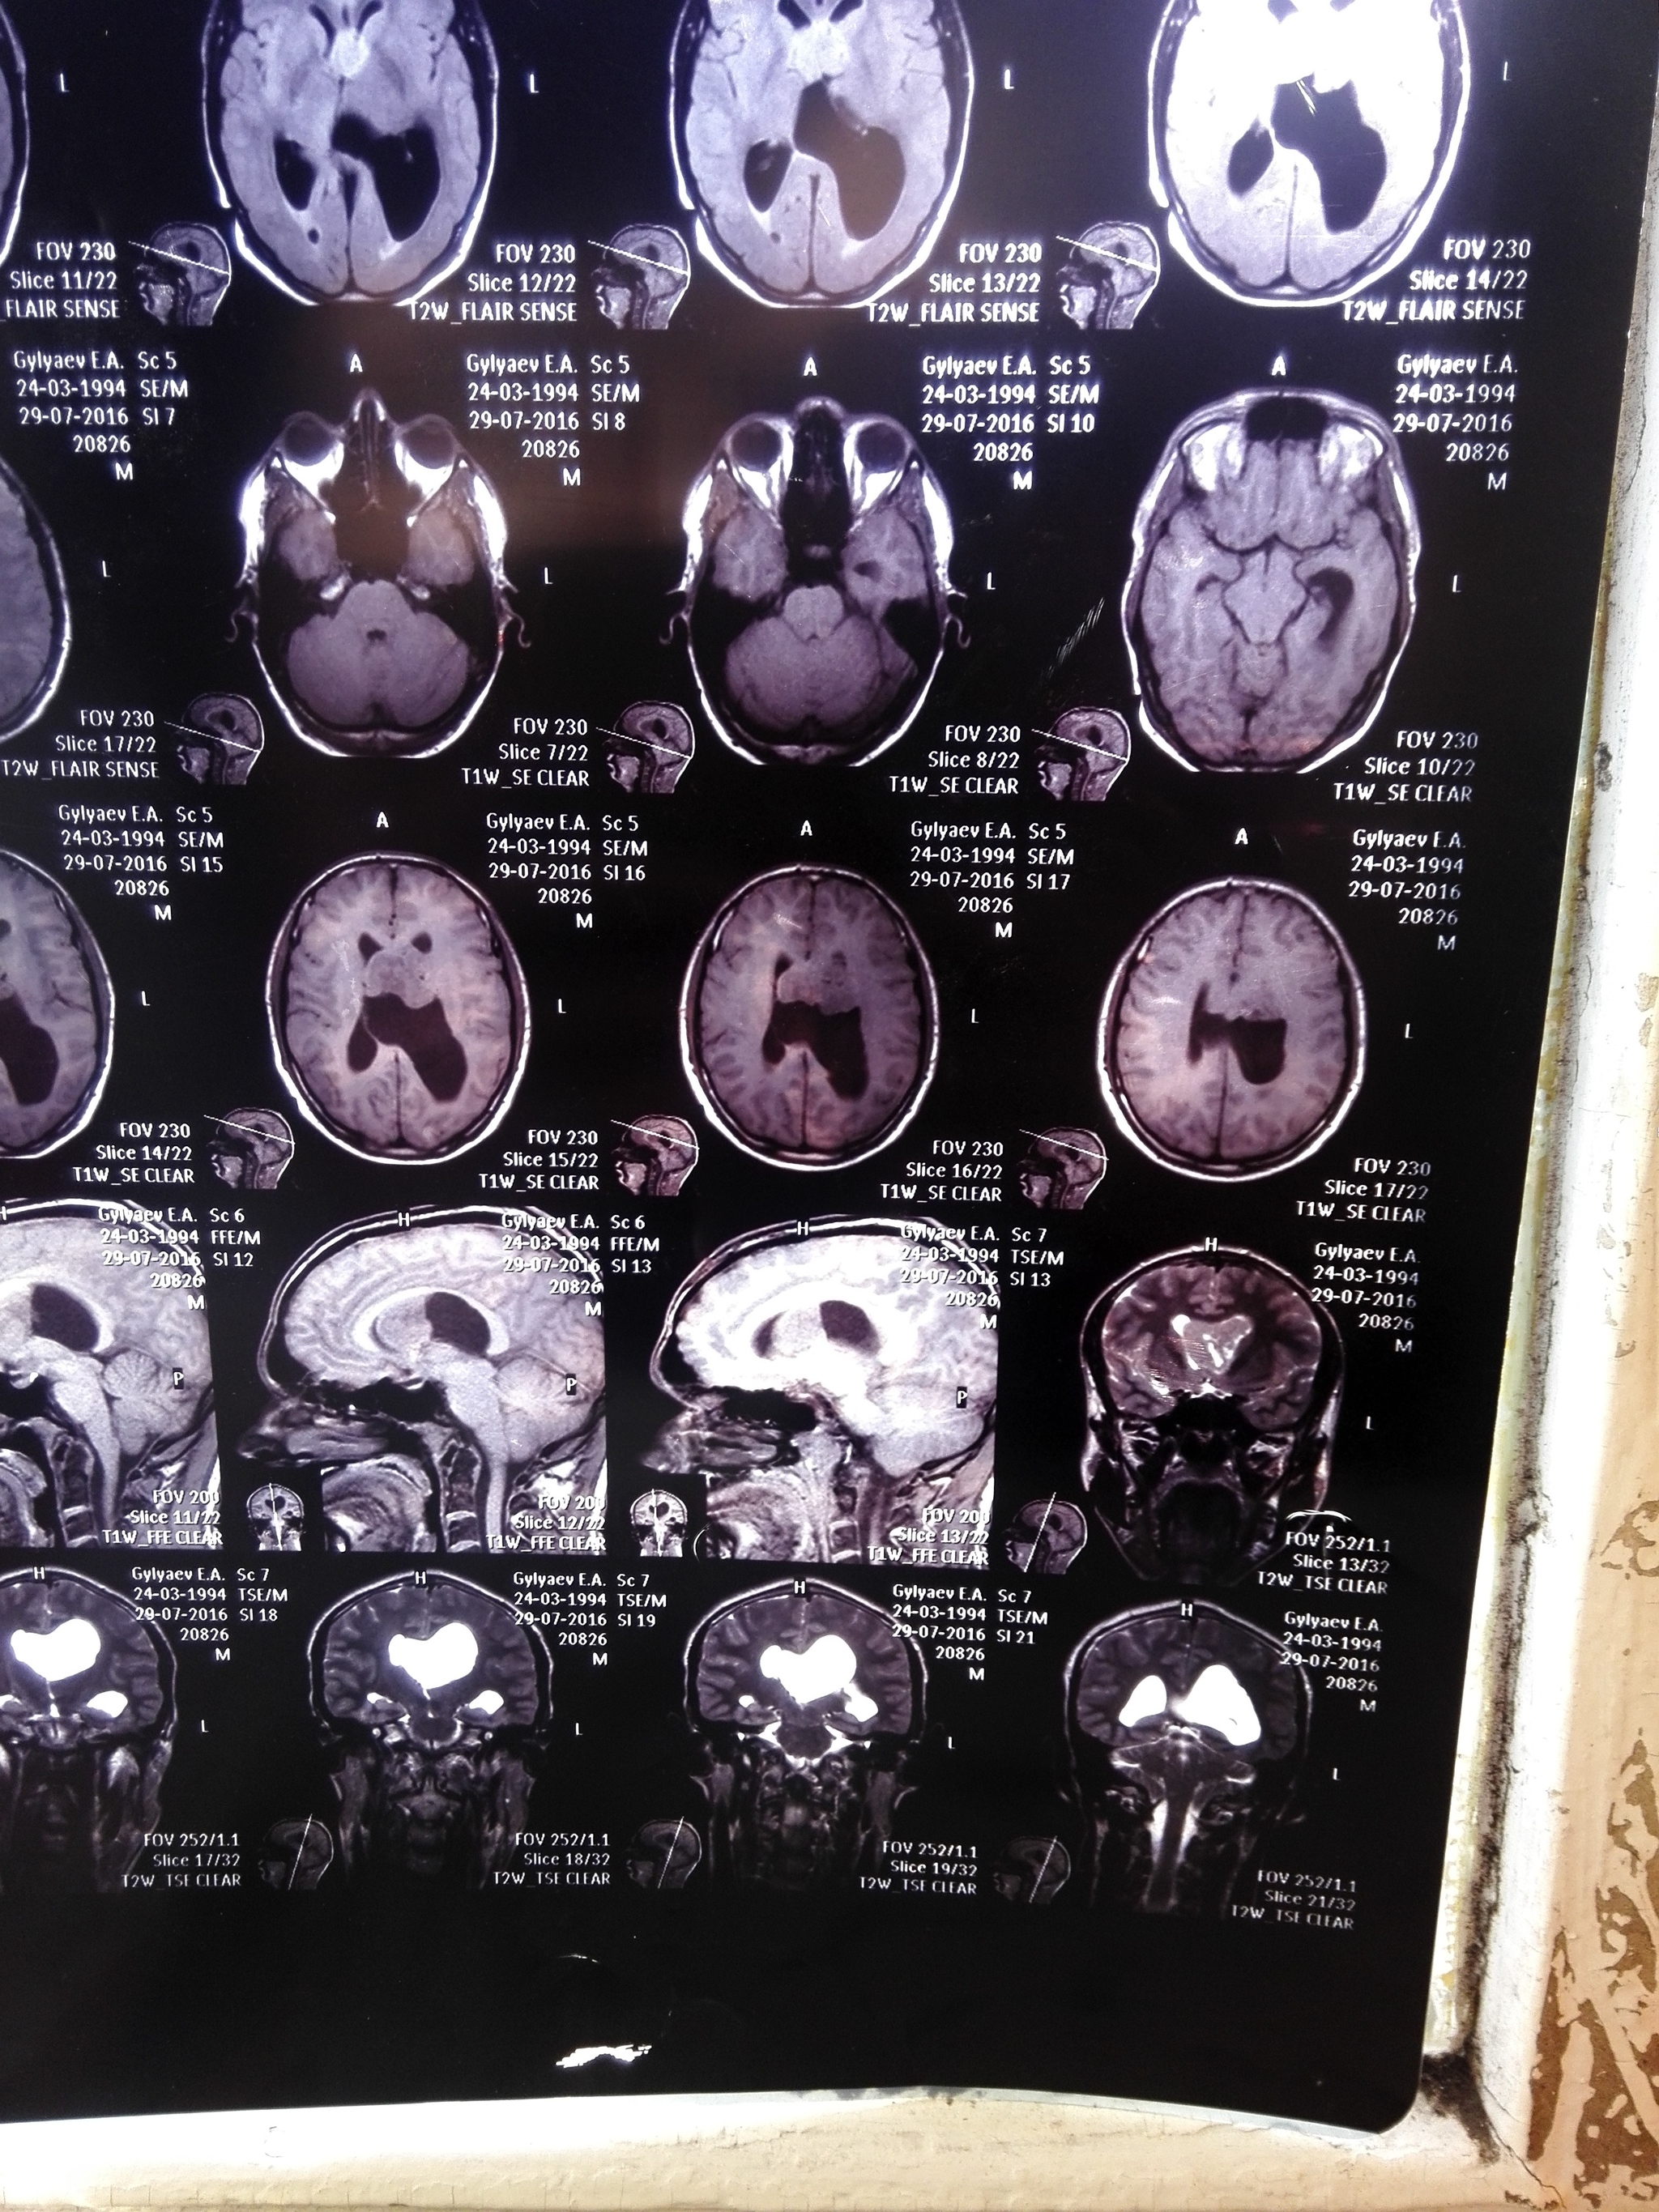

15 ноября ,к слову через день после моего 33 дня рождения я находилась дома одна с новорождённым ребёнком и у меня резко начало гореть лицо , пошло ощущение мурашек по носу и губам , ужасное чувство , помню его как сейчас , через пару часов стало как то сильно плохо и я побежала звать на помощь , добежать смогла до коридора , открыла дверь и нрохнулась в обморок на затылок , до сих пор помню звук как я падаю , перед падением увидела своё лицо в отражении двери, помню, что лицо как то все скривило , потекли слюни и я упала , ещё тогда подумала , что это инсульт и мне хана . Слава Богу свекровь , что живёт по соседству услышала через стену ( стена у нас общая ) грохот,прибежала и вызвала скорую . Повезли меня на скорой на обследование (от которого я изначально упорно отказывалась , так как дома маленький ребёнок, но в итоге поехала ,ещё тогда свято верила , что это просто упадок сил и через пару часов поеду домой , как же я ошибалась . Сделали кучу обследований у всевозможных врачей, потом кт, мрт и мртс контрастом, вот на последнем выясняется ,что у меня опухоль головного мозга ,размером 6см , решают оставить меня больнице на дальнейшее обследование, дальше капельницы ,уколы, день за днём, готовят к операции и переводят в 1ю краевую больницу города Краснодара, туда я поступила вечером , меня сразу побрили на лысо , тупой бритвой ,без пены для бритья , пошкрябали весь череп , следующий день 20.11 к обеду меня увозят на операцию. Операции я не боялась, но ужасно боялась, что будет после , начиталась о последствиях и страшно было, что больше не смогу ходить или говорить и тд , операция прошла без последствий ,опухоль полностью удалили и отправили на биопсию . Состояние после операции ужасное , все болит , голова тяжёлая, обезболивающее по барабану вообще было. Встала и пошла я уже на 2й день ,уж очень не хотелось в туалет на утку ходить . 29.11 меня выписали и сообщили результаты биопсии, опухоль оказалась злокачественная, ху грейд 2 ,рак второй степени и придётся мне ещё пройти лучевую терапию. Сейчас нахожусь дома , дочку пришлось отдать моей тёти пока что , так как я сейчас с ней не справлюсь даже с помощью мужа . Постоянно болит и кружится голова , сил нет от слова совсем , ещё у меня немного проблемы с речью,тяну и подбираю слова ,память тоже стала не очень , одно и тоже спрашиваю по 10 раз и тут же забываю что уже спрашивала и что мне ответили в душ ,на прогулку и тд все делается только под присмотром , хочется начать жить как до трепанации , забрать ребёнка, вернуться к спорту ,но как понимаю мне это не скоро грозит . Если здесь есть кто проходил через эту операцию расскажите как восстанавливались , как долго были головокружения и упадок сил